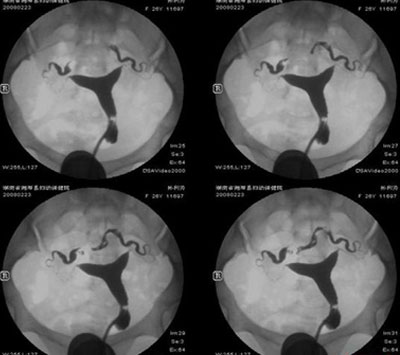

生殖系统检查:妇科B超(查子宫息肉、肌瘤、内膜厚度)、输卵管通畅度检查(如造影,视需求选)